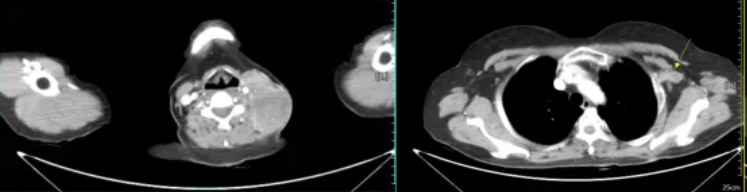

图7 左侧颈部、左侧胸廓入口、左侧腋窝CT示多发肿大淋巴结(2022-5-17)

2022年5月17日查颈部、胸部增强CT:食管中下段管壁稍增厚,较前大致相仿,左侧颈部、左侧胸廓入口处及左侧腋窝多发肿大淋巴结影,左侧胸廓入口处淋巴结较前大致相仿,余较前新增,考虑转移。疗效评价为疾病进展(PD)。